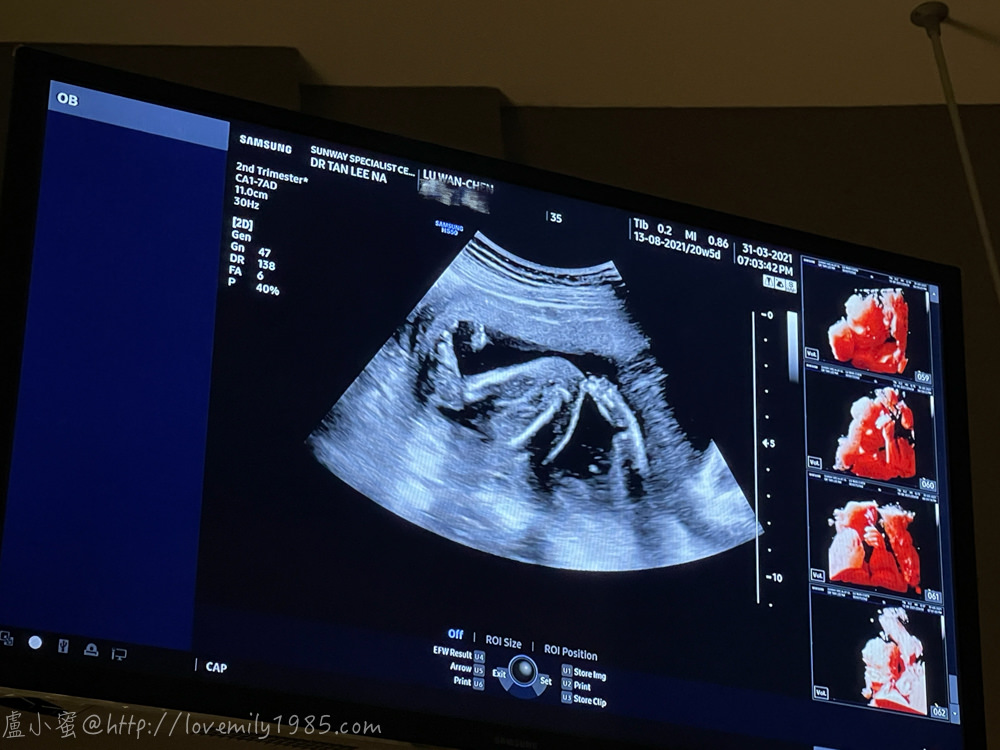

超清楚的手跟腿!除了檢查身體結構,醫生照了胎盤,說位置很好,可以自然生

好清楚的手指喔!

目前三寶體重約375g,是正常的進展!測量週數也跟實際週數差一兩天而已

晶21W5D照高層次的時候,約395g,好像差不多